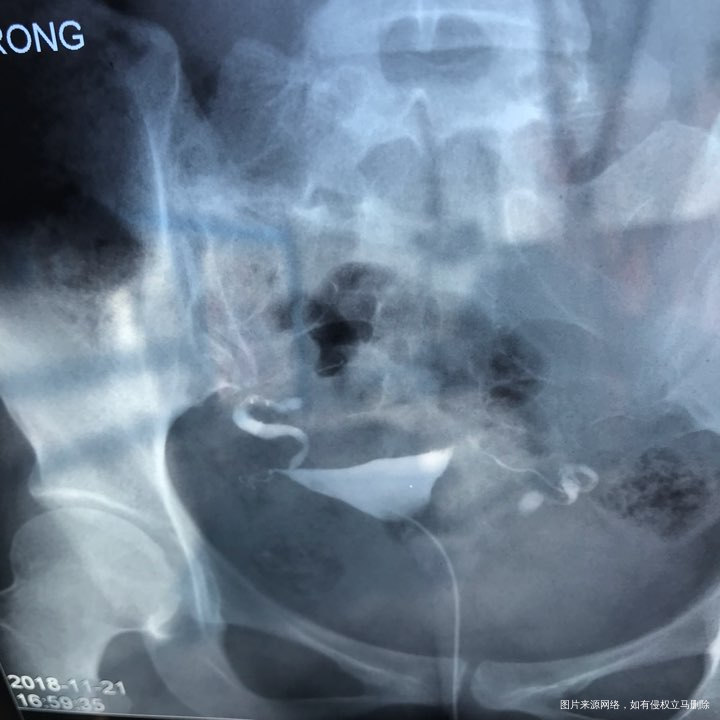

备孕时常1年,前期的检查都做了正常,帮忙看下我的输卵管造影片子吧??

您好,看着像是伞端堵塞了。

您好,考虑输卵管堵塞。建议遵医嘱。

您好,输卵管堵塞,建议切除输卵管做试管,保守保守治疗没有多大意义,觉着我的回复对您有帮助记着帮忙点击采纳,谢谢!